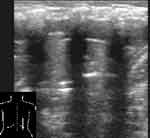

У новорожденных нередко отмечается «пестрая» картина с чередованием мелких безвоздушных и воздушных участков легкого. По-видимому, это связано с наличием множественных мелких ателектазов (Рис. 8). При острых пневмониях мы не наблюдали «локального плеврального выпота», выступающего в сторону легкого с неровным краем на границе легкого [2, 3]. Судя по приводимым снимкам авторы под видом выпота описывают собственно пневмонические очаги. Тем более, что как они сами указывают, рентгенологического и при направленной пункции подтверждения наличия выпота они не получили. Плевральный выпот, сопутствовавший острым пневмониям, по нашим наблюдениям в небольших количествах локализовался в синусах, большие его скопления могли поджимать нижние отделы легких, но локально он не выступал в сторону легкого и не имел неровного края на границе с легким. Чувствительность эхографии в диагностике пневмоний и ателектазов высока 89 — 100% [4, 8], поскольку безвоздушные участки практически всегда соприкасаются с поверхностью легкого вследствие конической формы легочных сегментов, обращенных основанием к плевре.

[Увеличить]

Рис. 8. Пневмония у новорожденного.